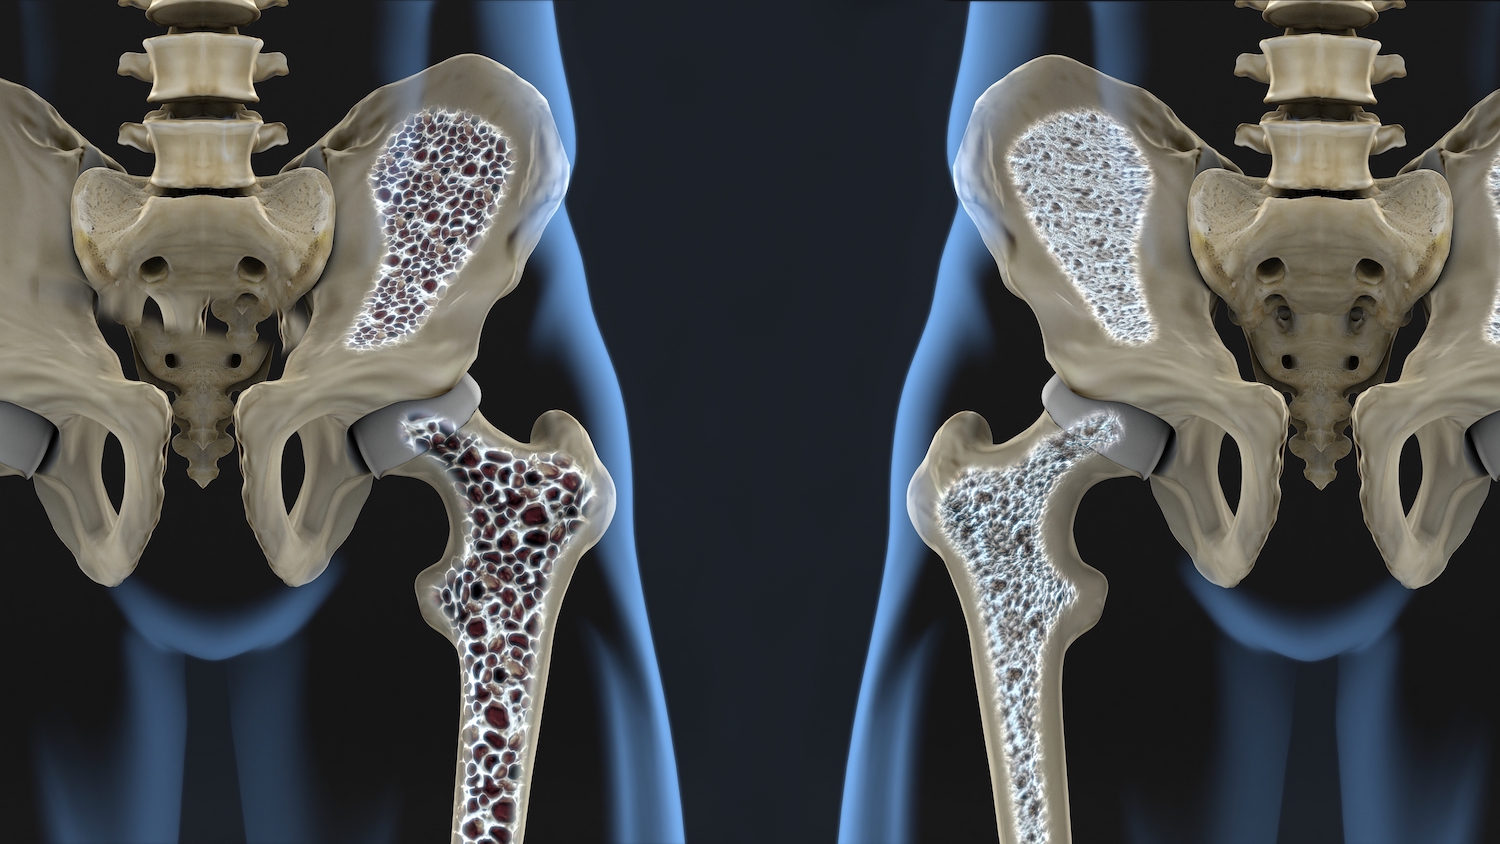

Adesea oasele afectate sunt cele de la nivelul bazinului, șoldului, a încheieturilor și a oaselor spatelui (coloana vertebrală). Deoarece această afecțiune reprezintă o degradare treptată și lentă a oaselor, mulți oameni o încadrează în categoria bolilor silențioase.

Bazinul și șoldul sunt adesea zone afectate de către osteoporoză

Cu tratament se poate ajunge la un echilibru între construcții și distrugeri